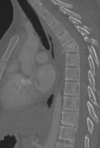

Fratura compressiva da coluna lombar

Causa achatamento do corpo e acunhamento geralmente anterior.

Tipo mais comum de fratura da coluna lombar

Estável.

Mecanismo flexão anterior ou lateral